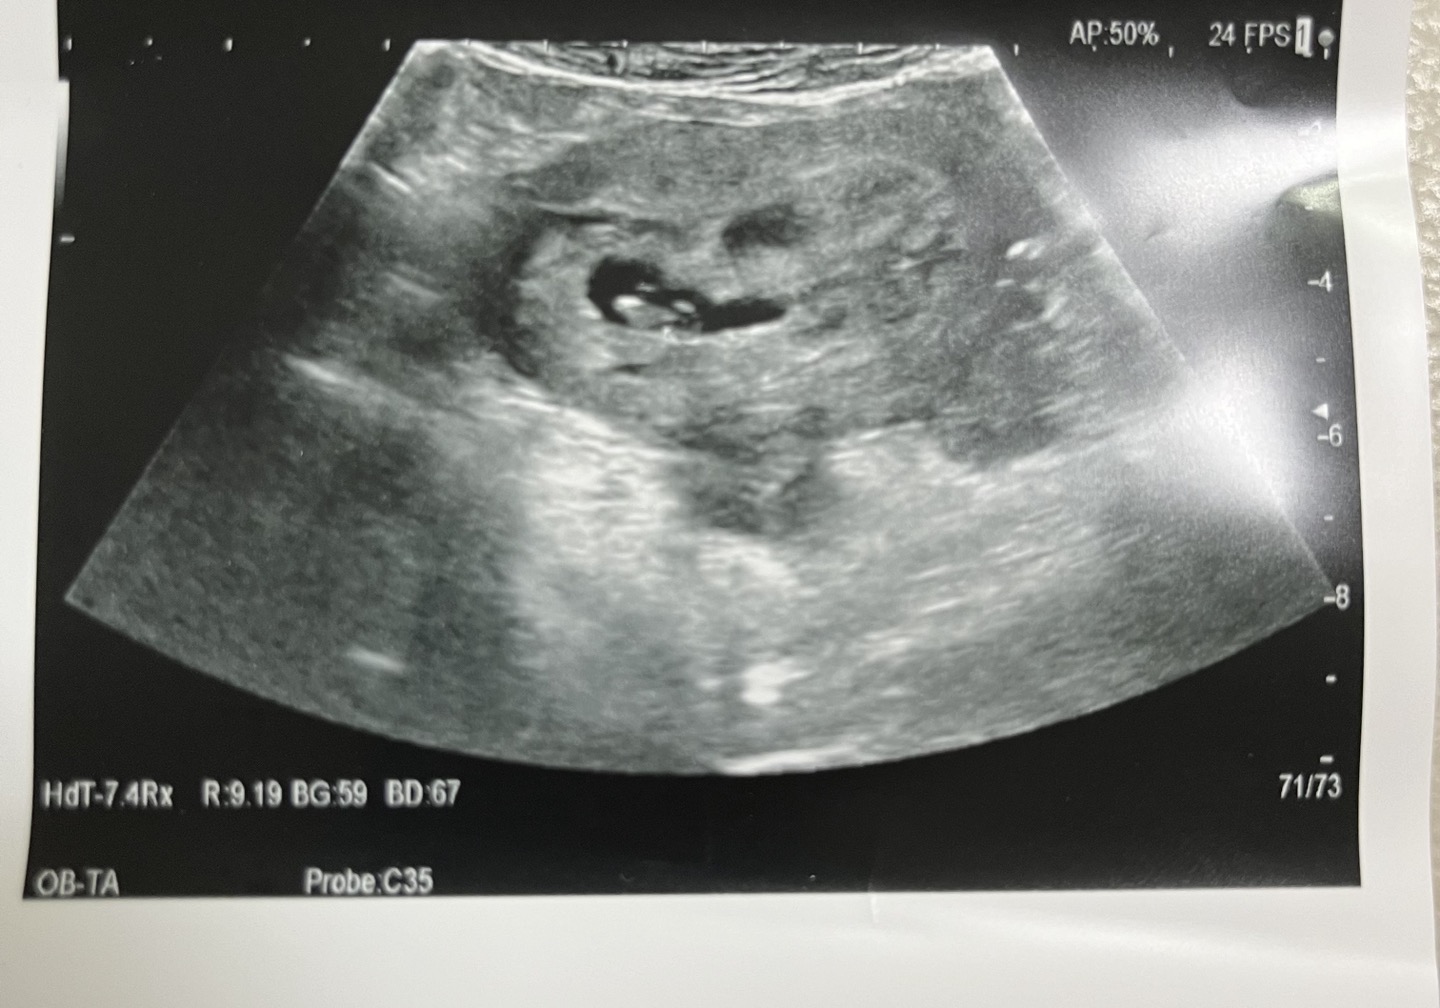

초음파로는 아기집 두 개 중 하나에서 아기가 보였고 나머지 하나는 빈 아기집만 보이는 상태였다.

쌍둥이임신을 했는데 다른 아기 하나는 늦게 크는걸까...?